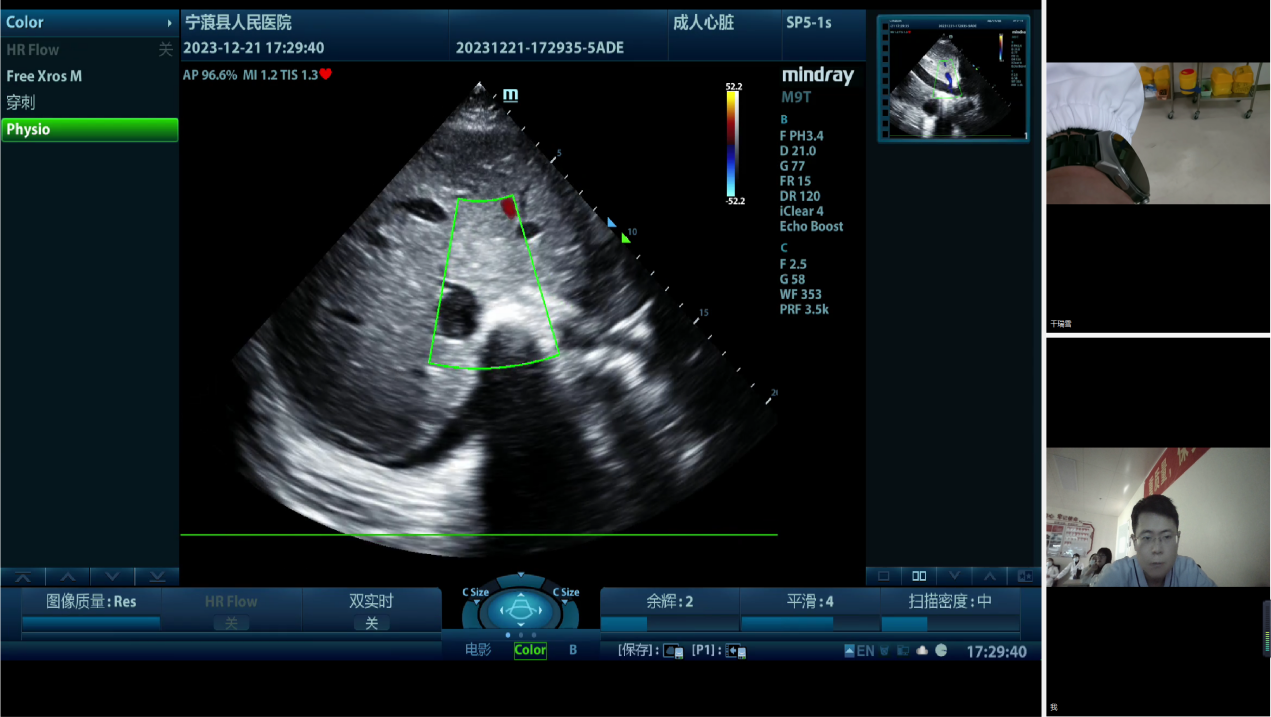

为进一步讨论治疗方案,宁蒗彝族自治县人民医院重症医学科通过“重症超声远程质控会诊平台”邀请昆医大附二院、丽江市人民医院重症医学科专家及院内专家多学科联合会诊。昆医大附二院重症医学科万林骏教授、万晓红主任医师、朱炜华副主任医师分别针对循环、呼吸、器官保护等提出治疗建议,并与丽江市人民医院重症医学科陈一峰科主任等专家讨论了下一步优化治疗的方案。